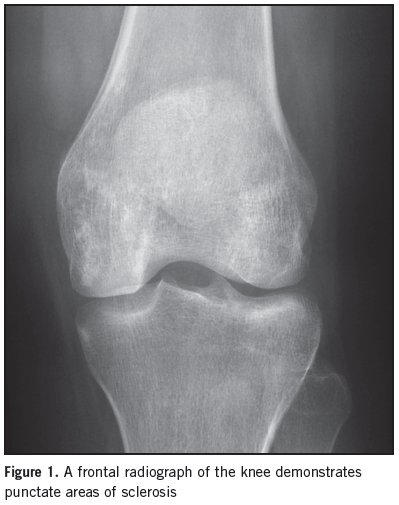

Radiology Quiz

William Yaakob, MD

A 26-year-old female comes to your office complaining of chronic left knee pain that has worsened over the last one to two weeks. She describes the pain as, “throbbing and aching.”